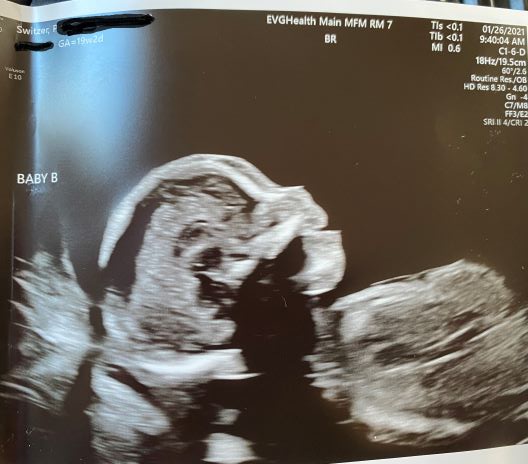

01/26/2021: 19w2d Dopplers return to normal but sIUGR diagnosis confirmed

With normalized Dopplers, this week the TAPS diagnosis is put on the back burner along with TTTS. However, sIUGR is confirmed because Baby A’s growth falls below the 10th percentile, the diagnosis of Selective Intrauterine Growth Restriction (sIUGR) is confirmed. While sIUGR and our babies have Type 3.